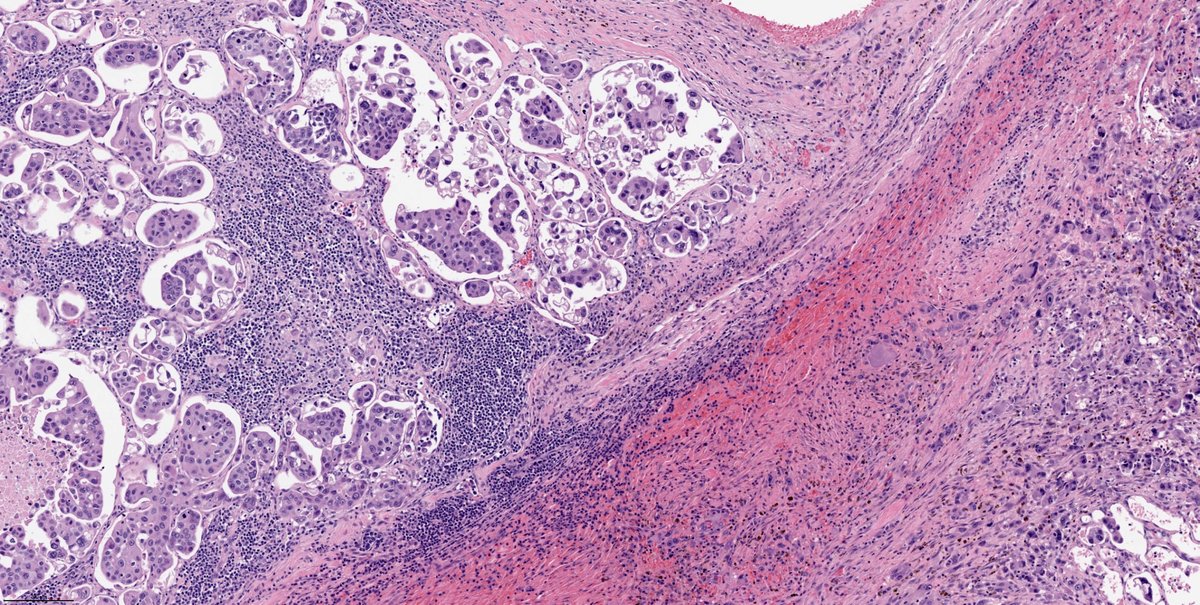

Hot off the press!! Check out this paper by Dr. Brandwein and team: Tall cell variant papillary thyroid carcinoma impacts disease-free survival at the 10 % cut-point on multivariate a… pubmed.ncbi.nlm.nih.gov/35834884/ #HeadAndNeckPath #ENTPath #ThyroidPath